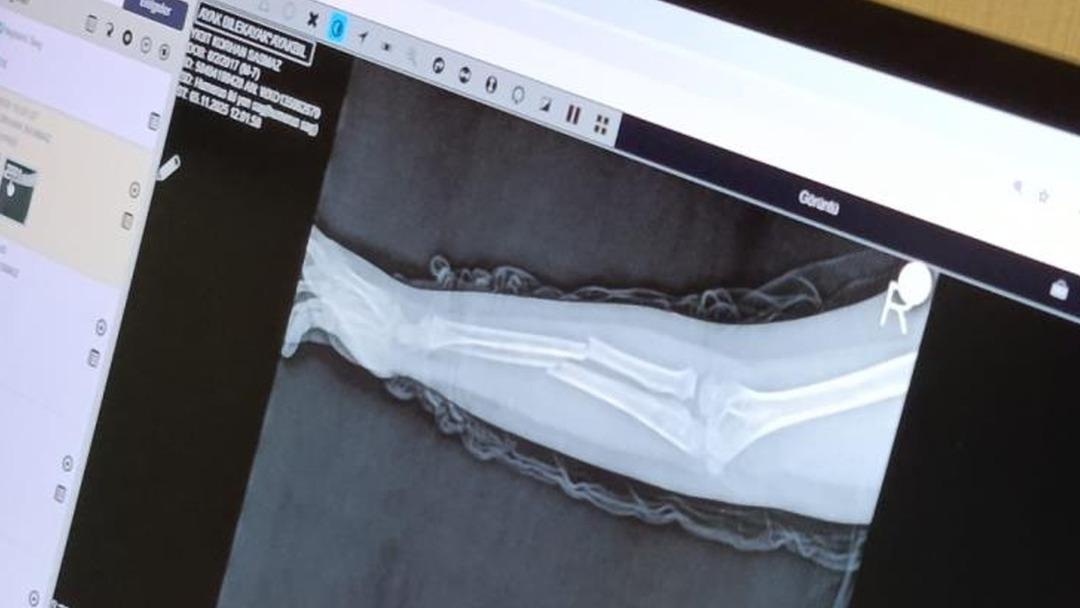

Y.K.Ş.'nin 2'ye katlanan kolu 2 ayrı yerinden kırıldı. Öğretmenler Y.K.Ş.'nin ailesini arayarak, ‘oğlunuz arkadaşıyla kavga etti duvara çarptı' denildi. Oğlunu okuldan alıp hastaneye götüren anne Songül Gökdemir, oğlunun kolunun 2 ayrı yerinden kırıldığını öğrenip ameliyata alınacağını duyduğunda büyük şok yaşadı.

Konuyla ilgili anne Gökdemir savcılığa giderek şikayetçi oldu. Savcılıktan ise 'söz konusu Suça Sürüklenen Çocuğun yaşının 12'den küçük olduğu gerekçesi ile kovuşturmaya yer yoktur' kararı çıktı. Anne Gökdemir karara itiraz ederken mağdur Y.K.Ş. ise haftalardır okula gidemiyor. Eğitimi aksayan çocuğun 2 hafta sonra ise platinlerinin çıkarılması için yeniden ameliyata gireceği öğrenildi.

Yaşanan olayı anlatan Songül Gökdemir, " Arkadaşlarından darbe aldığını biliyordum. Ayrıca Eylül ayından bu yana bir arkadaşının onun kolunu kırmaya çalıştığını söyledi. Ben de 'arkadaşını öğretmene söyle' dedim. Bundan kaçıyordu. O gün de rehber öğretmenine bu arkadaşını şikayet ettiler. Ben işe gittim 1 saat sonra öğretmeni aradı. Oğlunuz arkadaşıyla birbirini itekledi kolunu duvara çarptı gelir misiniz ?' dedi. Kendi imkanımla hastaneye götürdüm. Okula gittiğimde de oğlum derste oturuyordu. Öğretmen ders işliyordu ambulans çağırılmamış. Hastanede kolunda 2 tane kırık olduğunu acilen de ameliyata girmesi gerektiğini öğrendim. 3 gün sonra ameliyata alındı. Kolundaki platinlerden dolayı her gün pansumanı var. 2 hafta sonra tekrar ameliyatı var" dedi.